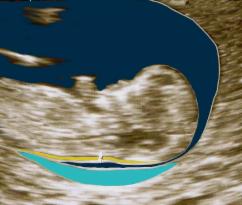

Im Bild rechts ist die Nackentransparenz schematisch dargestellt: es ist der schmale gelbe Streifen. Die fälschliche Messung des hellblauen Feldes oder des dunkelblauen Streifens dazwischen würde zu Fehlinterpretationen und vermeidbarer Beunruhigung der werdenden Eltern führen.